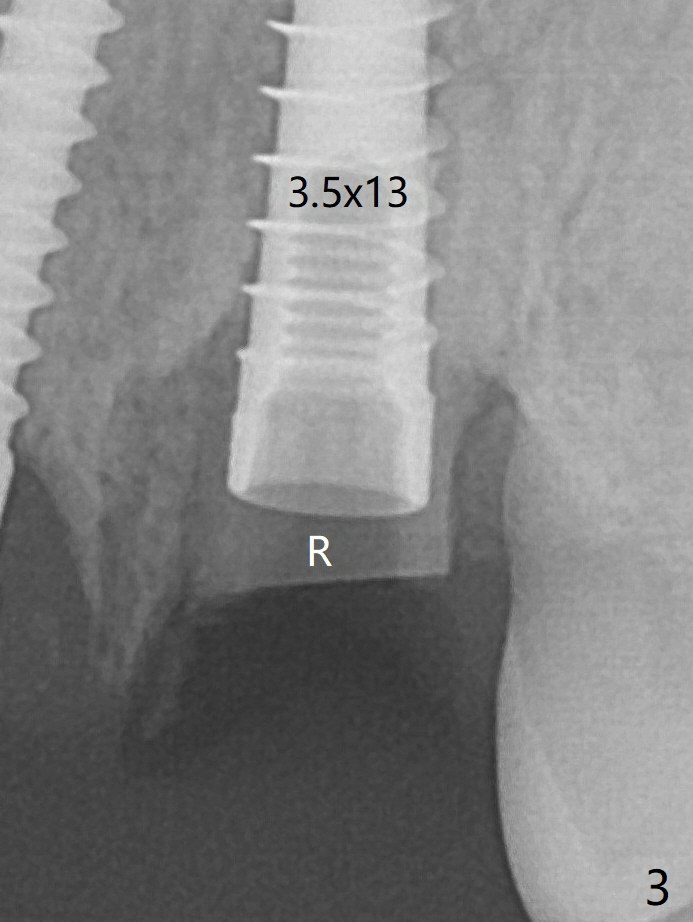

The socket shield at #11 is apparently incomplete, since the apical gutta percha (Fig.2 <) and the apex of the root (Fig.2,3 R) are not removed. The bone is hard when a 1.6 mm drill is being used (Fig.2) as the apical native bone is almost exclusively composed of the cortices. Two of the apical threads of 3.5x13 mm implant are bent, while the implant is placed deeper than the osteotomy (Fig.3,7). After placement of a 4.5x15 degrees A (2mm) angled abutment and Vanilla graft (Fig.7 *), an immediate provisional is fabricated. There is smooth transition from the grafted bone to the native bone 4.5 months postop (Fig.10). Low Magnification, High Magnification of Fig.7,10.